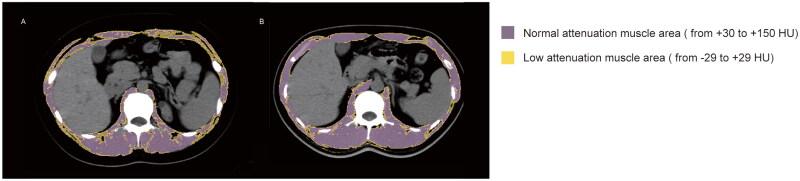

Totally 1,044 Chinese initial dialysis patients from four hospitals (2014-2020) were eventually enrolled and followed up to December 31, 2022 or until death in this retrospective cohort study. IATI was defined as the ratio of low attenuation muscle density to skeletal muscle density assessed by CT at the first lumbar vertebra level. Multivariate Cox regression and two-piecewise Cox proportional hazards models were used to determine the risk factors for all-cause mortality and to perform stratified analysis. Mediation analysis was conducted to identify mediators.